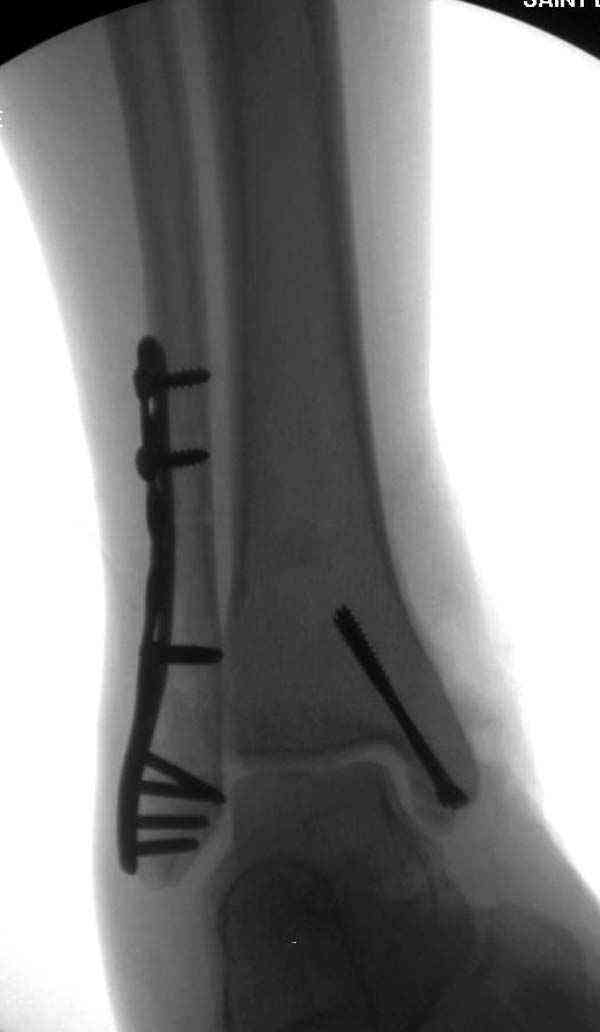

Случай прошлого года:пациентка-молодая ,крупная женщина ,30лет.Травма в начале апреля 2009г-пронационный перелом лодыжек с подвывихом стопы.Ко мне обратилась через 35 дней,прооперирована 22.05.2009г.Внутренняя лодыжка фиксирована по Веберу,наружная реконструктивной пластиной с наложением болта-стяжки.Иммобилизация "сапожок" в течении месяца,затем пригипсовано "стремя".Гипс снят 10.07.2009г

Достаточно быстрое восстановление функции.В октябре 2009г-почувствовала боль,в области рубца над гайкой открылся свищ.На Р-граммах-консолидация переломов и смещение гайки по стяжке.10.11.2009г-конструкции удалены,санация,заживление ран.В настоящее время пациентку ничего не беспокоит.На операции-раскручивание гайки-болталась на конце стяжки.Вопросы:какой механизм раскручивания и что я неправильно сделал?Свои версии:1)в области синдесмоза успела образоваться рубцовая ткань,которая при движении в суставе"пружинила",поскольку голеностопный сустав является спиральным, то и биомеханика подобна кривошипному механизму.2)Реконструктивная пластина не "реконструировалась" по форме лодыжки.Наложил,как есть.То есть подпружинивала сама пластина.Ну,это мои догадки.Что нужно,чтобы избегать впредь таких,пусть и не "страшных"осложнений:Рассверливать через лодыжку область синдесмоза?Ставить шайбу-гровер?Тщательно моделировать пластину?Прилагаю сравнительные снимки-сразу после операции и перед удалением конструкции.

Визуально никаких вопросов по репозиции не было.Да и на основании чего сомнения,что наружная лодыжка не полностью репонирована или прорезалась проволка ???Я не вижу...Снимок после репозиции справа.

Раз ,есть желание посмотреть другую проекцию выкладываю-ну лучшего качества нет...

Нет первичных снимков, перелом очень низкий и под большим сомнением диагноз разрыва синдесмоза. Медиальная сторона отрепонирована на "хорошо" и, по-видимому, прорезание проволоки произошло во время операции. Без снимков трудно судить о высоте малоберцовой, а лодыжка находится в варусе. Лагирование получилось, но возле тонких шурупов передне-задний шуруп выглядит немного тяжеловато.